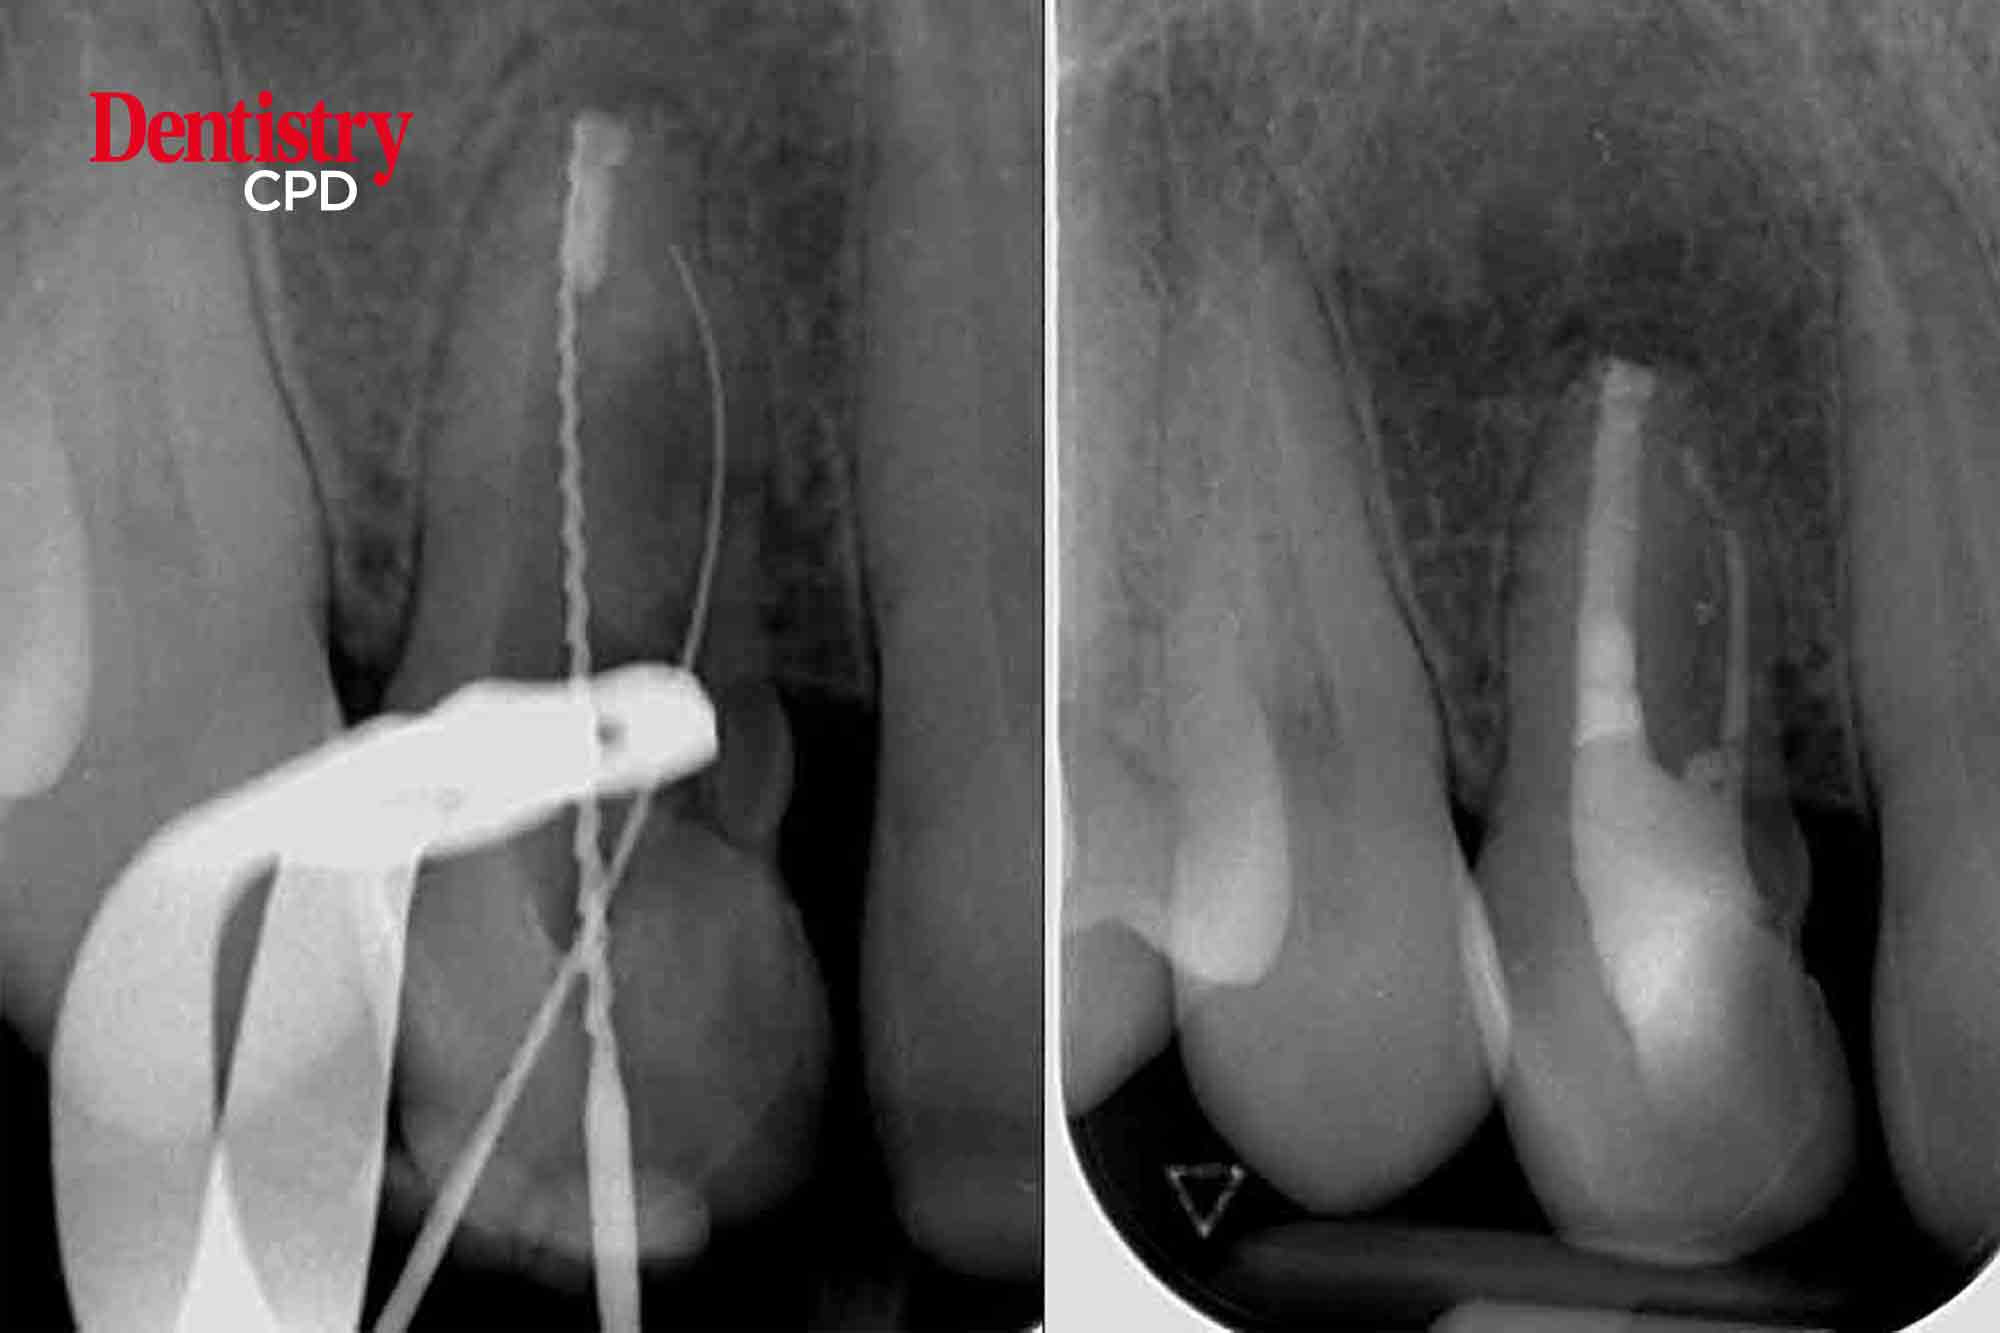

John Rhodes looks at the non-surgical retreatment of a maxillary lateral incisor with unusual anatomy; a second root and canal

To show treatment planning and decision making process for endodontic retreatment of a lateral incisor with an unusual extra root and canal